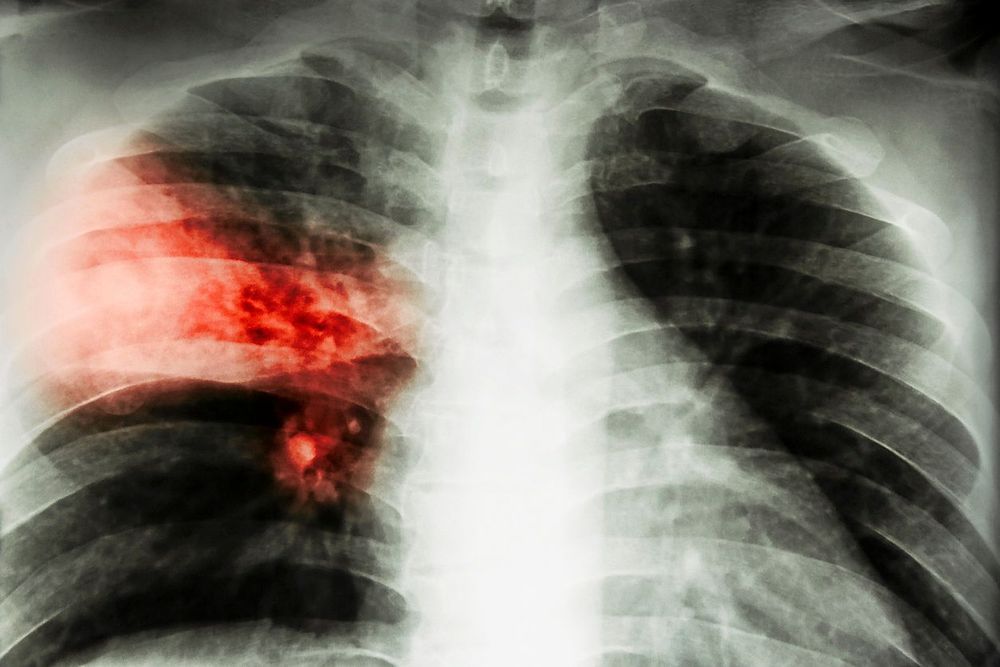

Lungornas luftblåsor angrips

Det som händer vid lunginflammation är att lungornas små luftblåsor, alveolerna, som absorberar syre nu fylls med slem och vätska och blir inflammerade. Då reagerar kroppen med hosta för att få upp slemmet. Feber är också vanligt.